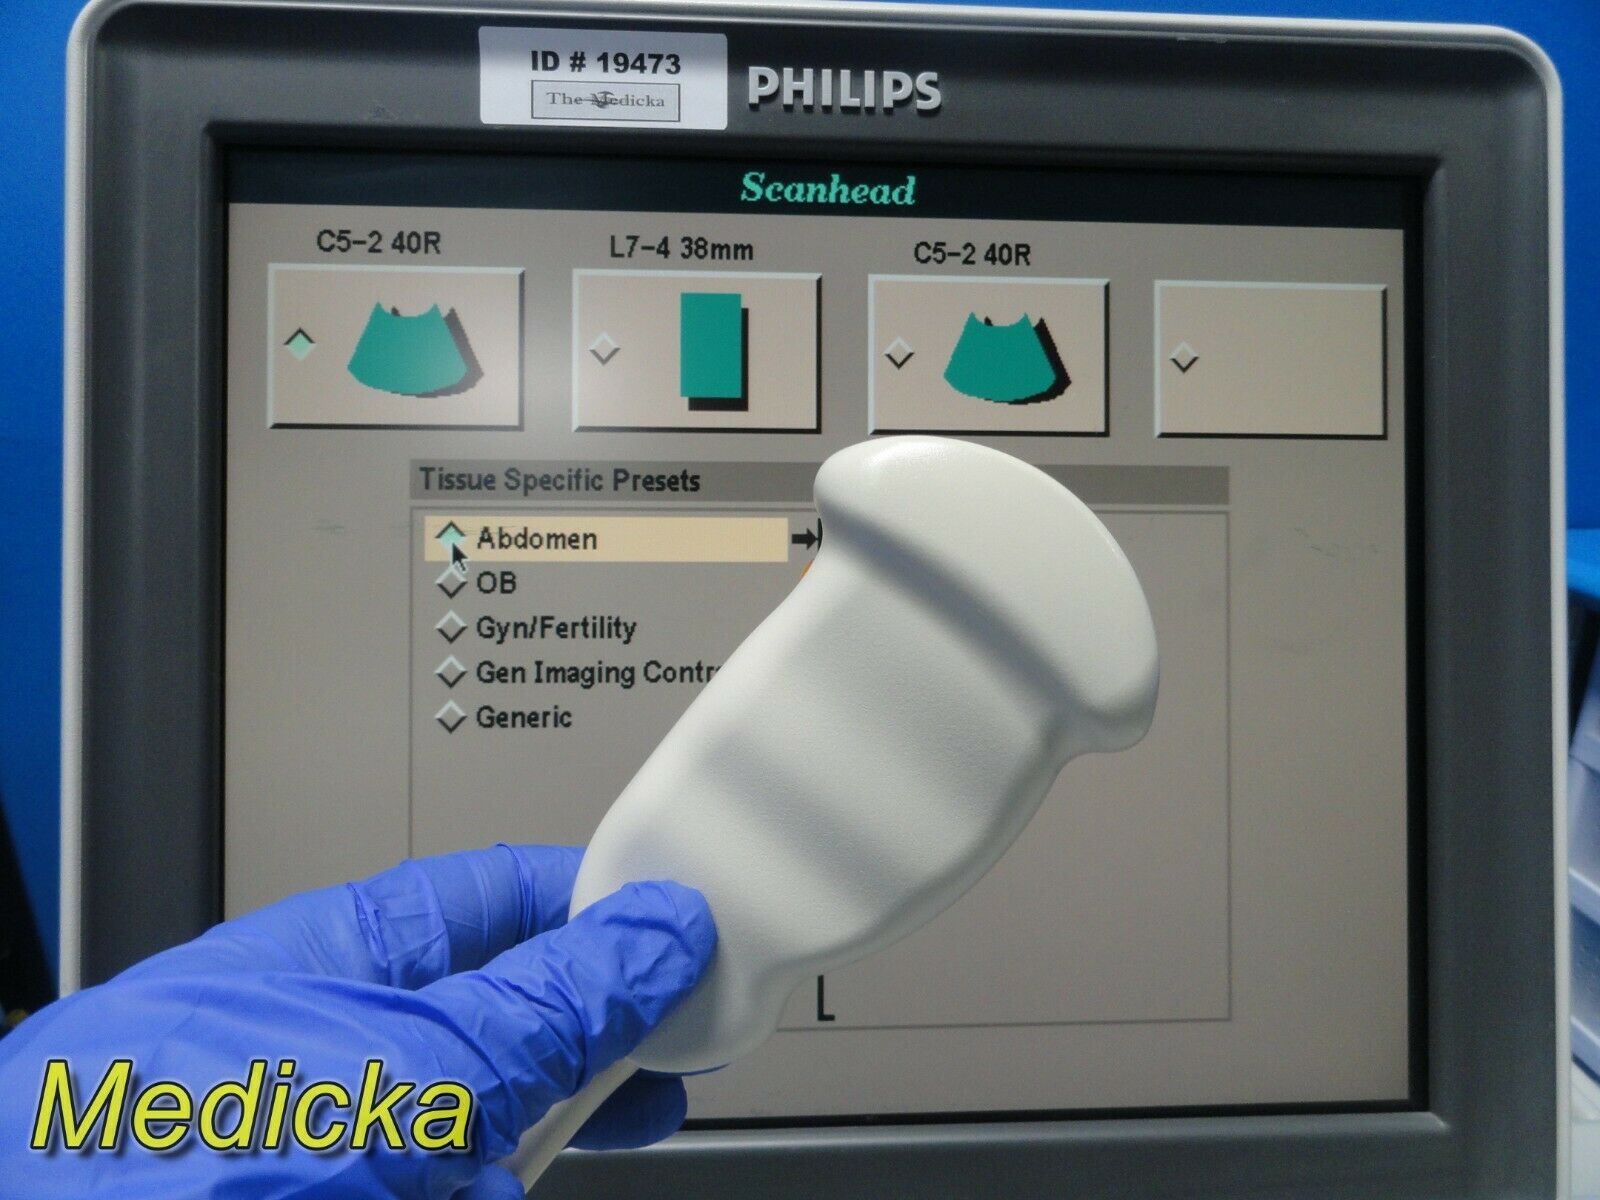

DIAGNOSTIC ULTRASOUND MACHINES FOR SALE

PHILIPS ULTRASOUND TRANSDUCER S4-1 PROBE

Sale price$ 1,228.36

DIAGNOSTIC ULTRASOUND MACHINES FOR SALE

PHILIPS S12-4 ULTRASOUND TRANSDUCER PROBE

Sale price$ 4,305.00